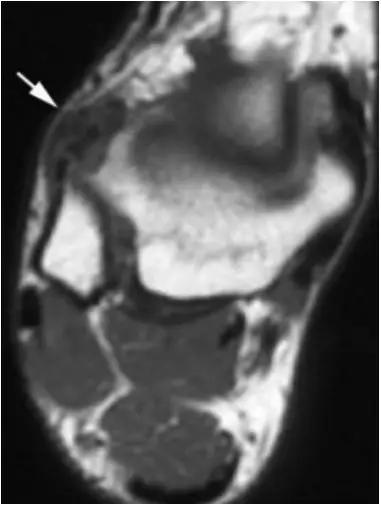

- 影像学表现为距骨后三角骨的存在或损伤以及距骨后突骨赘形成,导致踝关节跖屈受限,可伴随拇长屈肌肌腱鞘炎症及邻近滑膜不同程度的炎性增生 。

正常后踝韧带;MRI 冠状位T2-FLAIR示踝间后韧带(长箭)

男,11岁,自述后踝下方疼痛,活动时为甚,并有一突起。

- MRI 检查示距后三角骨及周围软组织有水肿信号,距后三角骨和距骨之间正常的低信号纤维连接中断,出现液性信号。

3、MR表现:

- 三角籽骨或距骨后三角结构模糊和变形,T1WI信号降低, T2WI信号升高,

- 周围脂肪水肿,

- 踇趾长屈肌腱信号升高,见鞘膜积液,

- 胫骨后下跟骨上缘骨结构形态变化和信号异常,

- 三角籽骨和距骨退行性囊变。